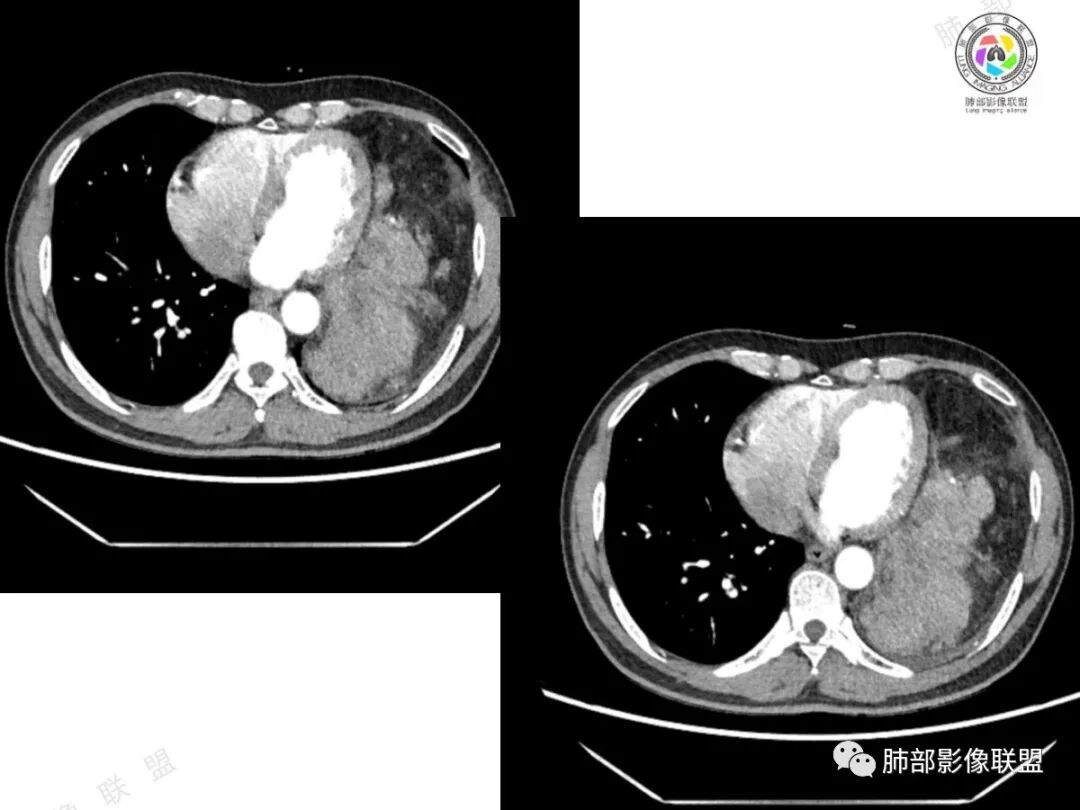

2、影像所见:左侧纵隔紧贴心包铸型生长巨大混杂密度肿块,边界清楚,临近结构受推挤移位,无明显外侵征象。肿块自主动脉弓旁一直顺延到至膈顶,呈“垂乳征”。病灶脂肪成分居多,斑片状、结节状及团块状实性密度成分散落其中,呈地图样分布,实性成分偶见低密度线样分隔,未见明确钙化影。增强扫描实性成分呈延迟明显强化,并见强化血管影。纵隔内有肿大淋巴结,未见胸腔积液,肺内及胸膜未见转移性病灶。

3、影像诊断:脂肪肉瘤?胸腺脂肪瘤?畸胎瘤?胸腺瘤?

①脂肪肉瘤:本例含较多脂肪组织,需考虑分化成熟型脂肪肉瘤(高分化型)的可能,其好发于前中纵隔的下部及心膈角区,肿块常大,偏于一侧,可有分叶,包膜可完整,与周围组织器官界限清楚。以脂肪密度为主的肿块,增强后仅见间隔或实性部分轻微强化。而本例实性成分过多,且实性病灶强化较明显,与高分化型脂肪肉瘤表现矛盾。

②胸腺脂肪瘤:好发于前下纵隔心膈角区,肿块一般较大,多见于40岁以下年龄患者,其内可见条状或片絮状胸腺组织,一般无周围侵犯。本例实性成分多、体积大,年龄较大,与胸腺脂肪瘤存在较多冲突。